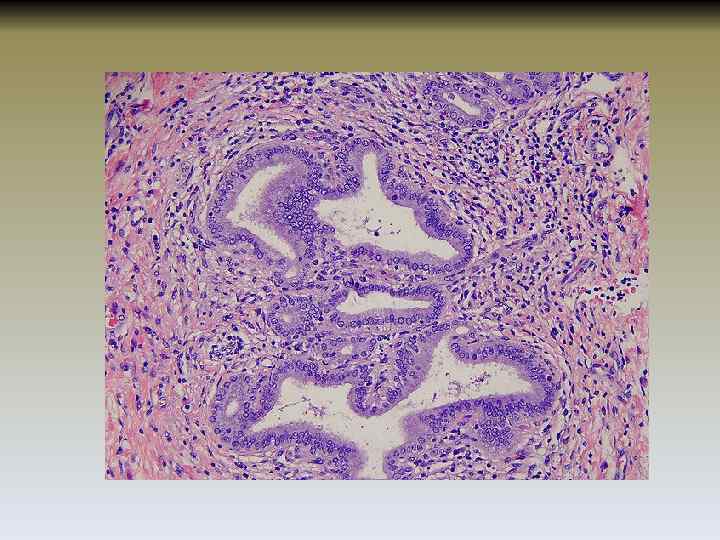

Классификация по гистологическим изменениям(критерии Ludwig and Scheuer) • I стадия. Начальная стадия. Дуктальная (стадия воспаления). Характеризуется лимфоплазмоклеточной инфильтрацией портальных трактов, разрушением эпителия желчных протоков и базальной мембраны. • II стадия. Прогрессирующее воспаление. Дуктулярная. Портальные тракты расширяются, развивается перипортальный фиброз. Могут обнаруживаться очаги воспаления, расположенные перипортально. Происходит пролиферация мелких желчных протоков. Фокальные некрозы. • III стадия. Септальный фиброз. Возникает септальный фиброз. Обнаруживаются признаки активного воспалительного процесса. Портальные тракты запустевают и замещаются рубцовой тканью. Возникают более обширные некрозы паренхимы. • IV. Терминальная. Мелкоузловой портальный цирроз